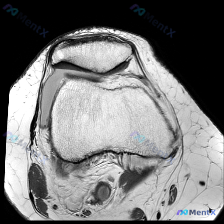

这是一张膝关节MRI-T2序列的轴位图像,扫描层面在髌股关节层面,可以清晰看到前方的髌骨、后方的股骨滑车以及周围支持带软组织。

- 骨性结构: 髌骨形态完整,骨皮质轮廓清晰,股骨滑车关节面形态可见,骨髓信号未见明显异常高信号,没有明确骨挫伤或骨坏死征象

- 关节软骨: 髌骨后关节面、股骨滑车关节面软骨信号,未见明显局限性高信号中断或缺失

- 韧带软组织: 髌骨内、外侧支持带走行连续,没有明显断裂或弥漫性高信号水肿,未见明确软组织包块

- 核心异常: 髌骨外侧关节囊区域可见明显液性高信号影,也就是关节积液,占据了髌骨外侧间隙大部分空间